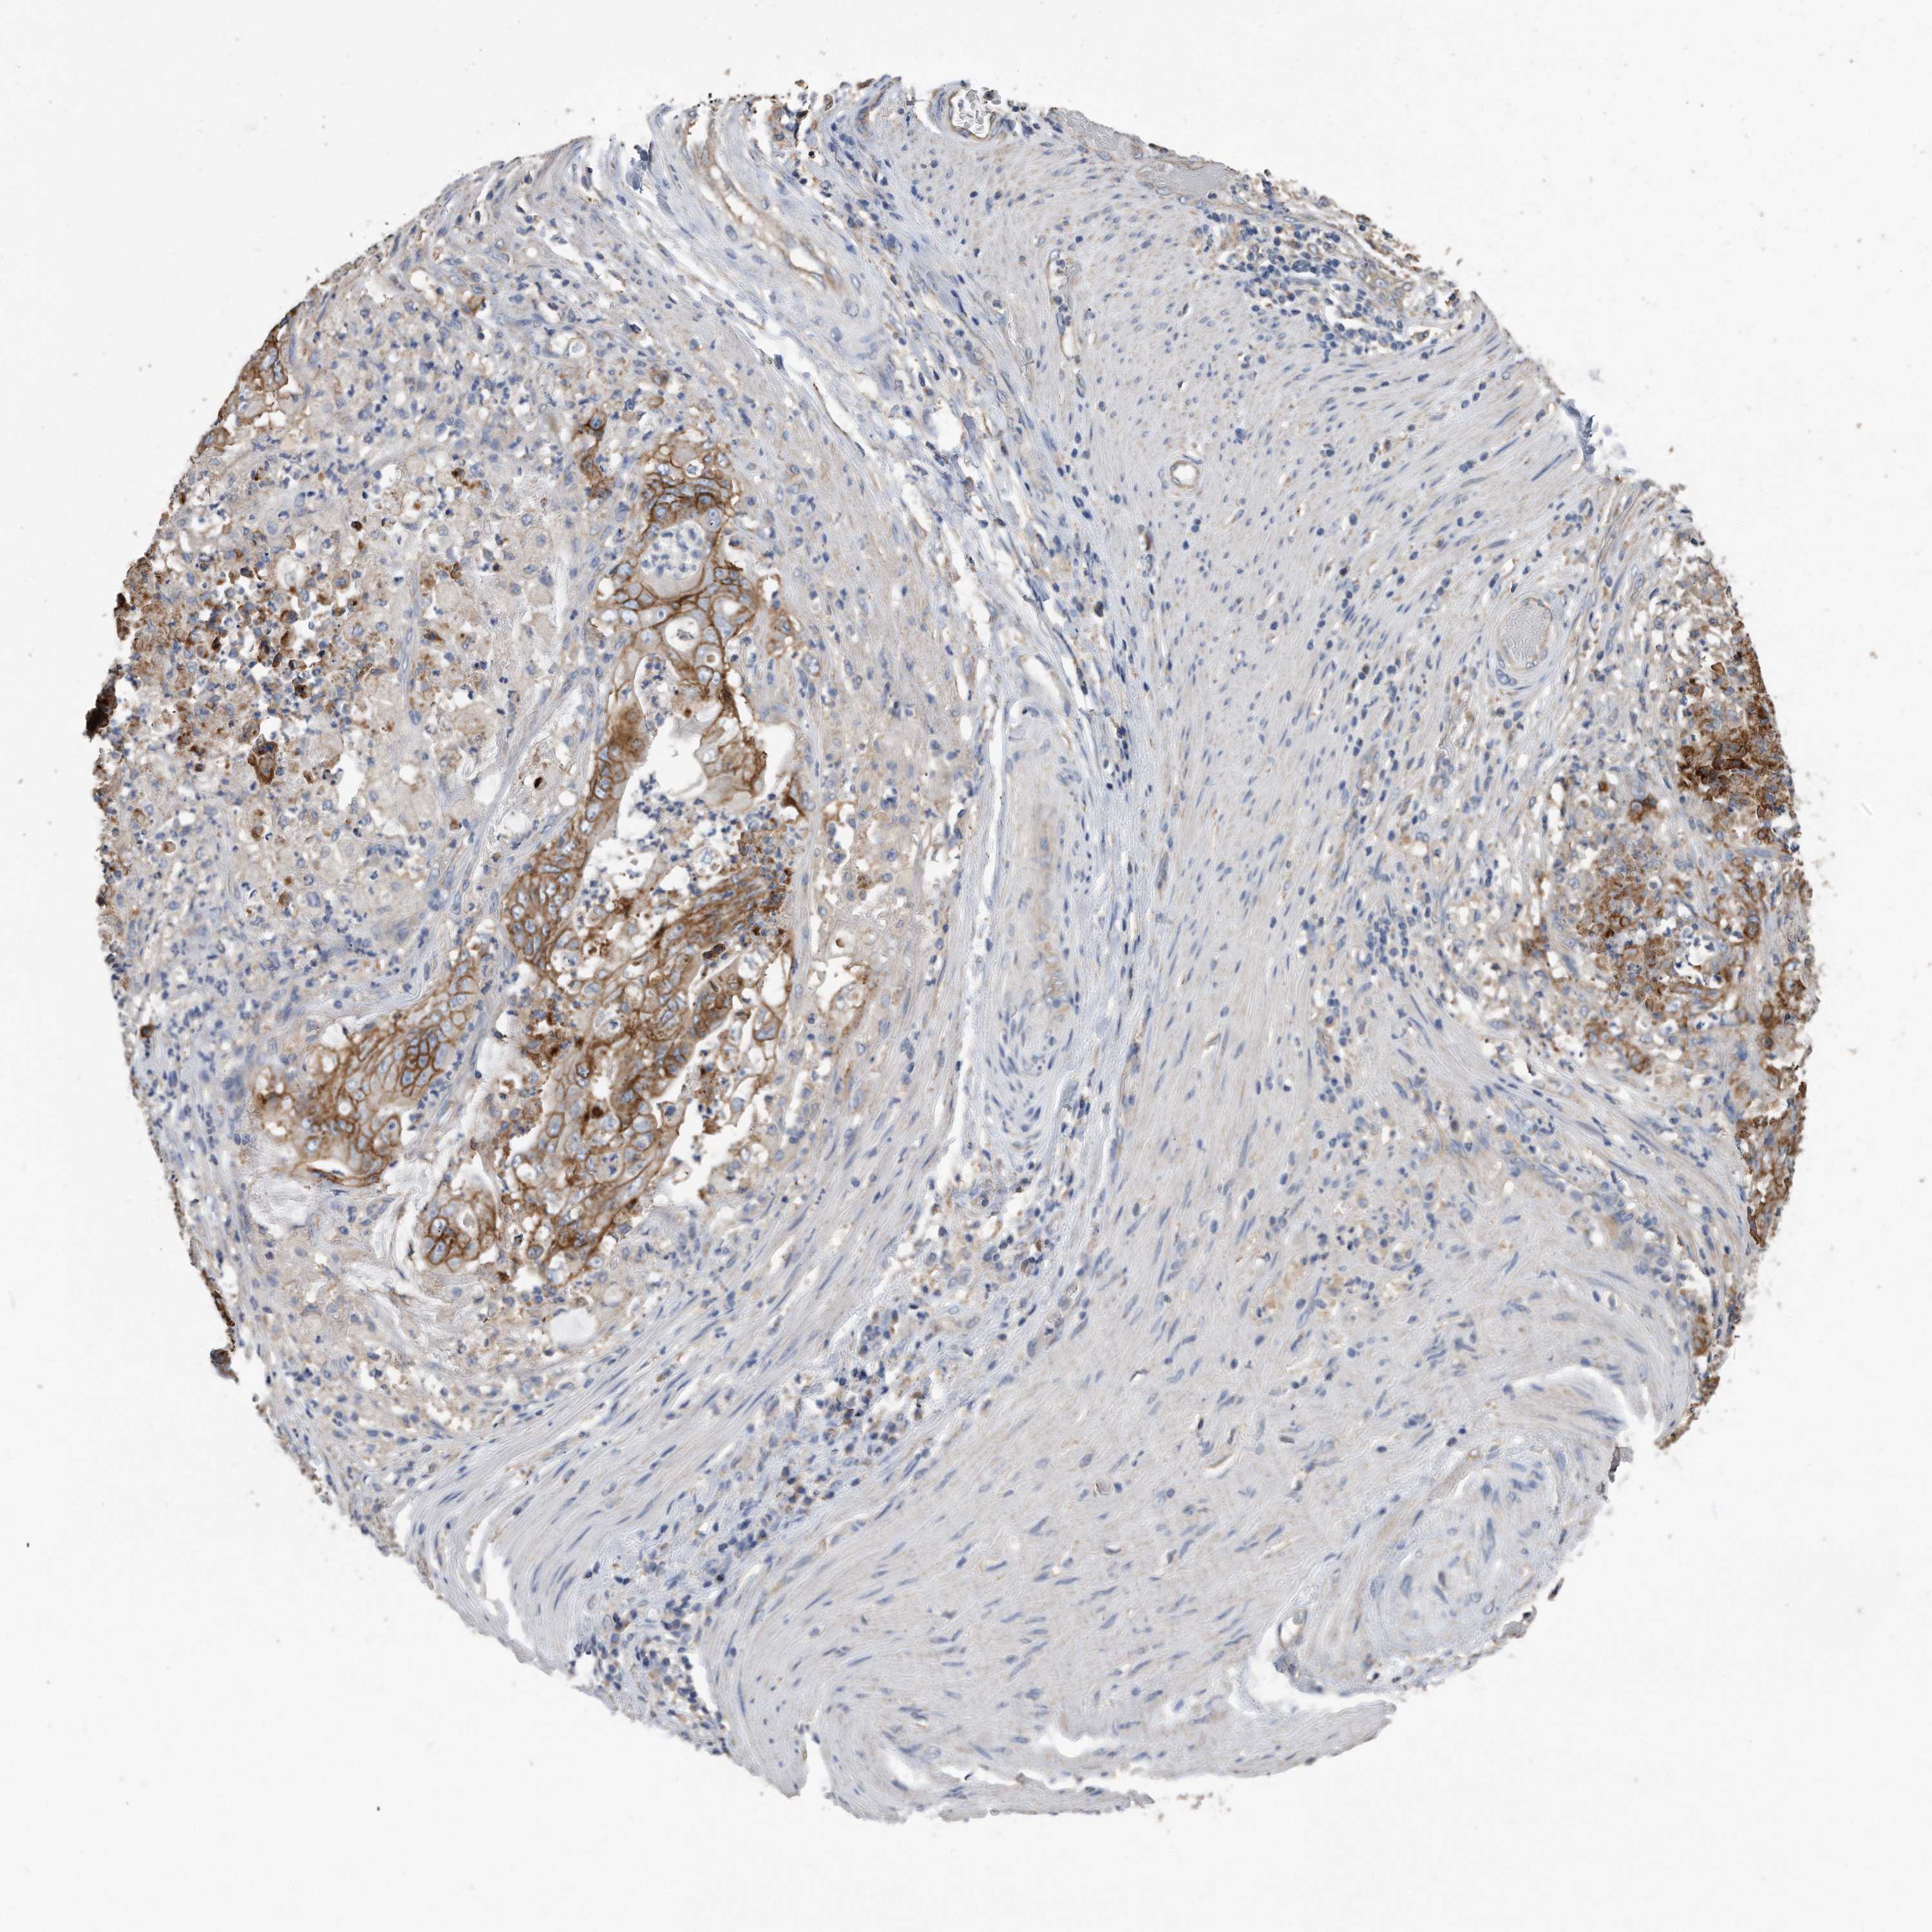

STOMACH CANCER - Protein expressioni

A mouse-over function shows sample information and annotation data. Click on an image to view it in a full screen mode. Samples can be filtered based on level of antibody staining by selecting one or several of the following categories: high, medium, low and not detected. The assay and annotation is described here.

Note that samples used for immunohistochemistry by the Human Protein Atlas do not correspond to samples in the TCGA dataset.

Antibody stainingi

Antibody staining in the annotated cell types in the current human tissue is reported as not detected, low, medium, or high, based on conventional immunohistochemistry profiling in selected tissues. This score is based on the combination of the staining intensity and fraction of stained cells.

Each image is clickable and will lead to virtual microscopy that enables deeper exploration of all samples and also displays staining intensity scores, fraction scores and subcellular localization as well as patient and tissue information for each sample.

Antibody HPA010978

Antibody HPA010979

Antibody CAB025637

Staining

High

Medium

Low

Not detected

Intensity

Strong

Moderate

Weak

Negative

Quantity

>75%

75%-25%

<25%

None

Location

Nuclear

Cytoplasmic/membranous

Cytoplasmic/membranous,nuclear

Adenocarcinoma, NOS

Adenocarcinoma, High grade